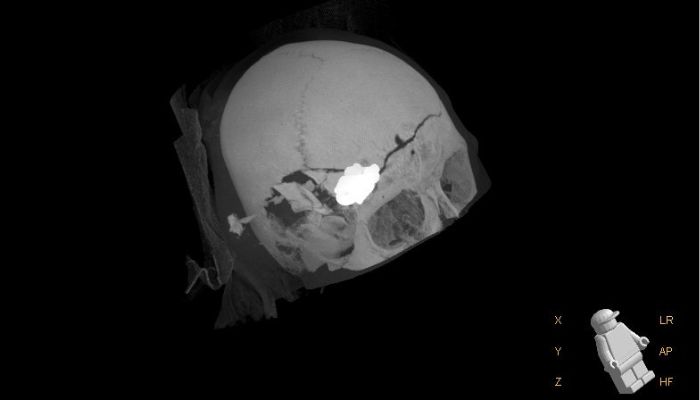

Das CT-Bild zeigt das rund 5 Zentimeter große Metallstück im Schädel von Felix. (Bild: SALK)

Der Junge aus Ainring (Bayern) erlitt bei einem Forstunfall am 28. Dezember 2023 schwere Verletzungen am Schädel. Ein Zugseil riss und ein Verbindungsstück aus Metall traf Felix am Kopf, wo es in der Schädeldecke stecken blieb. Es kam zu sofortigen Einbußen des Sehvermögens, der Junge blieb aber bei Bewusstsein. Nach Erster-Hilfe-Leistung der Angehörigen wurde Felix mit dem Hubschrauber ins Uniklinikum Salzburg transportiert. Durch eine Not-Operation konnte sein Zustand stabilisiert und das Metallteil entfernt werden, jedoch blieb ein großer, zerstörter Teil der Schädeldecke zurück. Der Junge befand sich im künstlichen Koma und die Angehörigen und Ärzte blieben mit etlichen Fragen zurück. Wie wirkt sich die Schwellung des Gehirns aus? Mit welchen neurologischen Schäden ist zu rechnen?